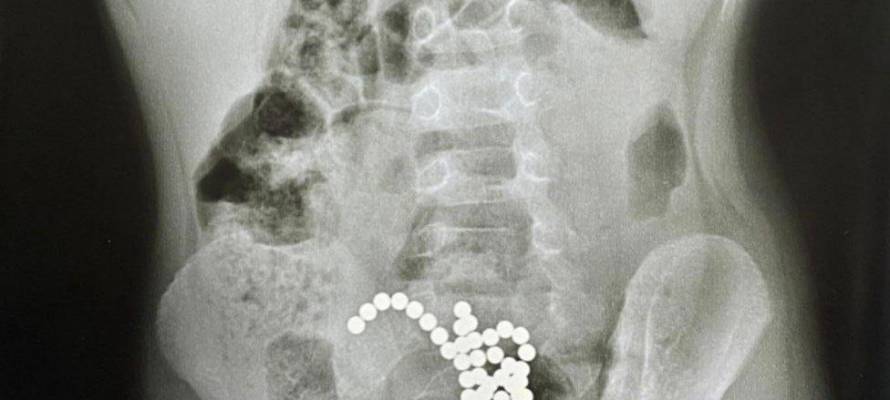

48 магнитов из кишечника годовалого ребенка достали хирурги детской краевой больницы №1 во Владивостоке, сообщает РИА VladNews со ссылкой на Краевой клинический центр специализированных видов медицинской помощи

«У годовалого ребёнка (только вслушайтесь!) было удалено 48 магнитов! И 18 — у трёхлетнего, – говорит она. – Вообще, что только не достают наши детские хирурги», — рассказала главный врач Краевой детской клинической больницы № 1 Инна Зеленкова.